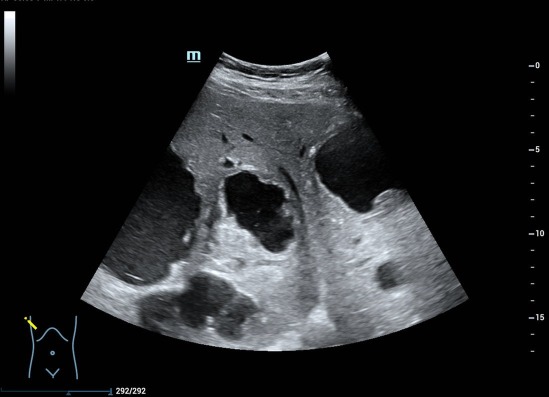

肝脏体积增大,右叶斜径约 19.0cm ,肝内可见多个厚壁无回声,大的位于肝右叶,大小约 15.5cmx13.9cm 的囊实性结节,内可见粗大分隔及壁结节,肝内胆管未见扩张。CDFI: 囊肿周边可见少许血流信号(图 1-5 )。

图 4 囊肿周边可见厚壁,类似「 面包圈 」征